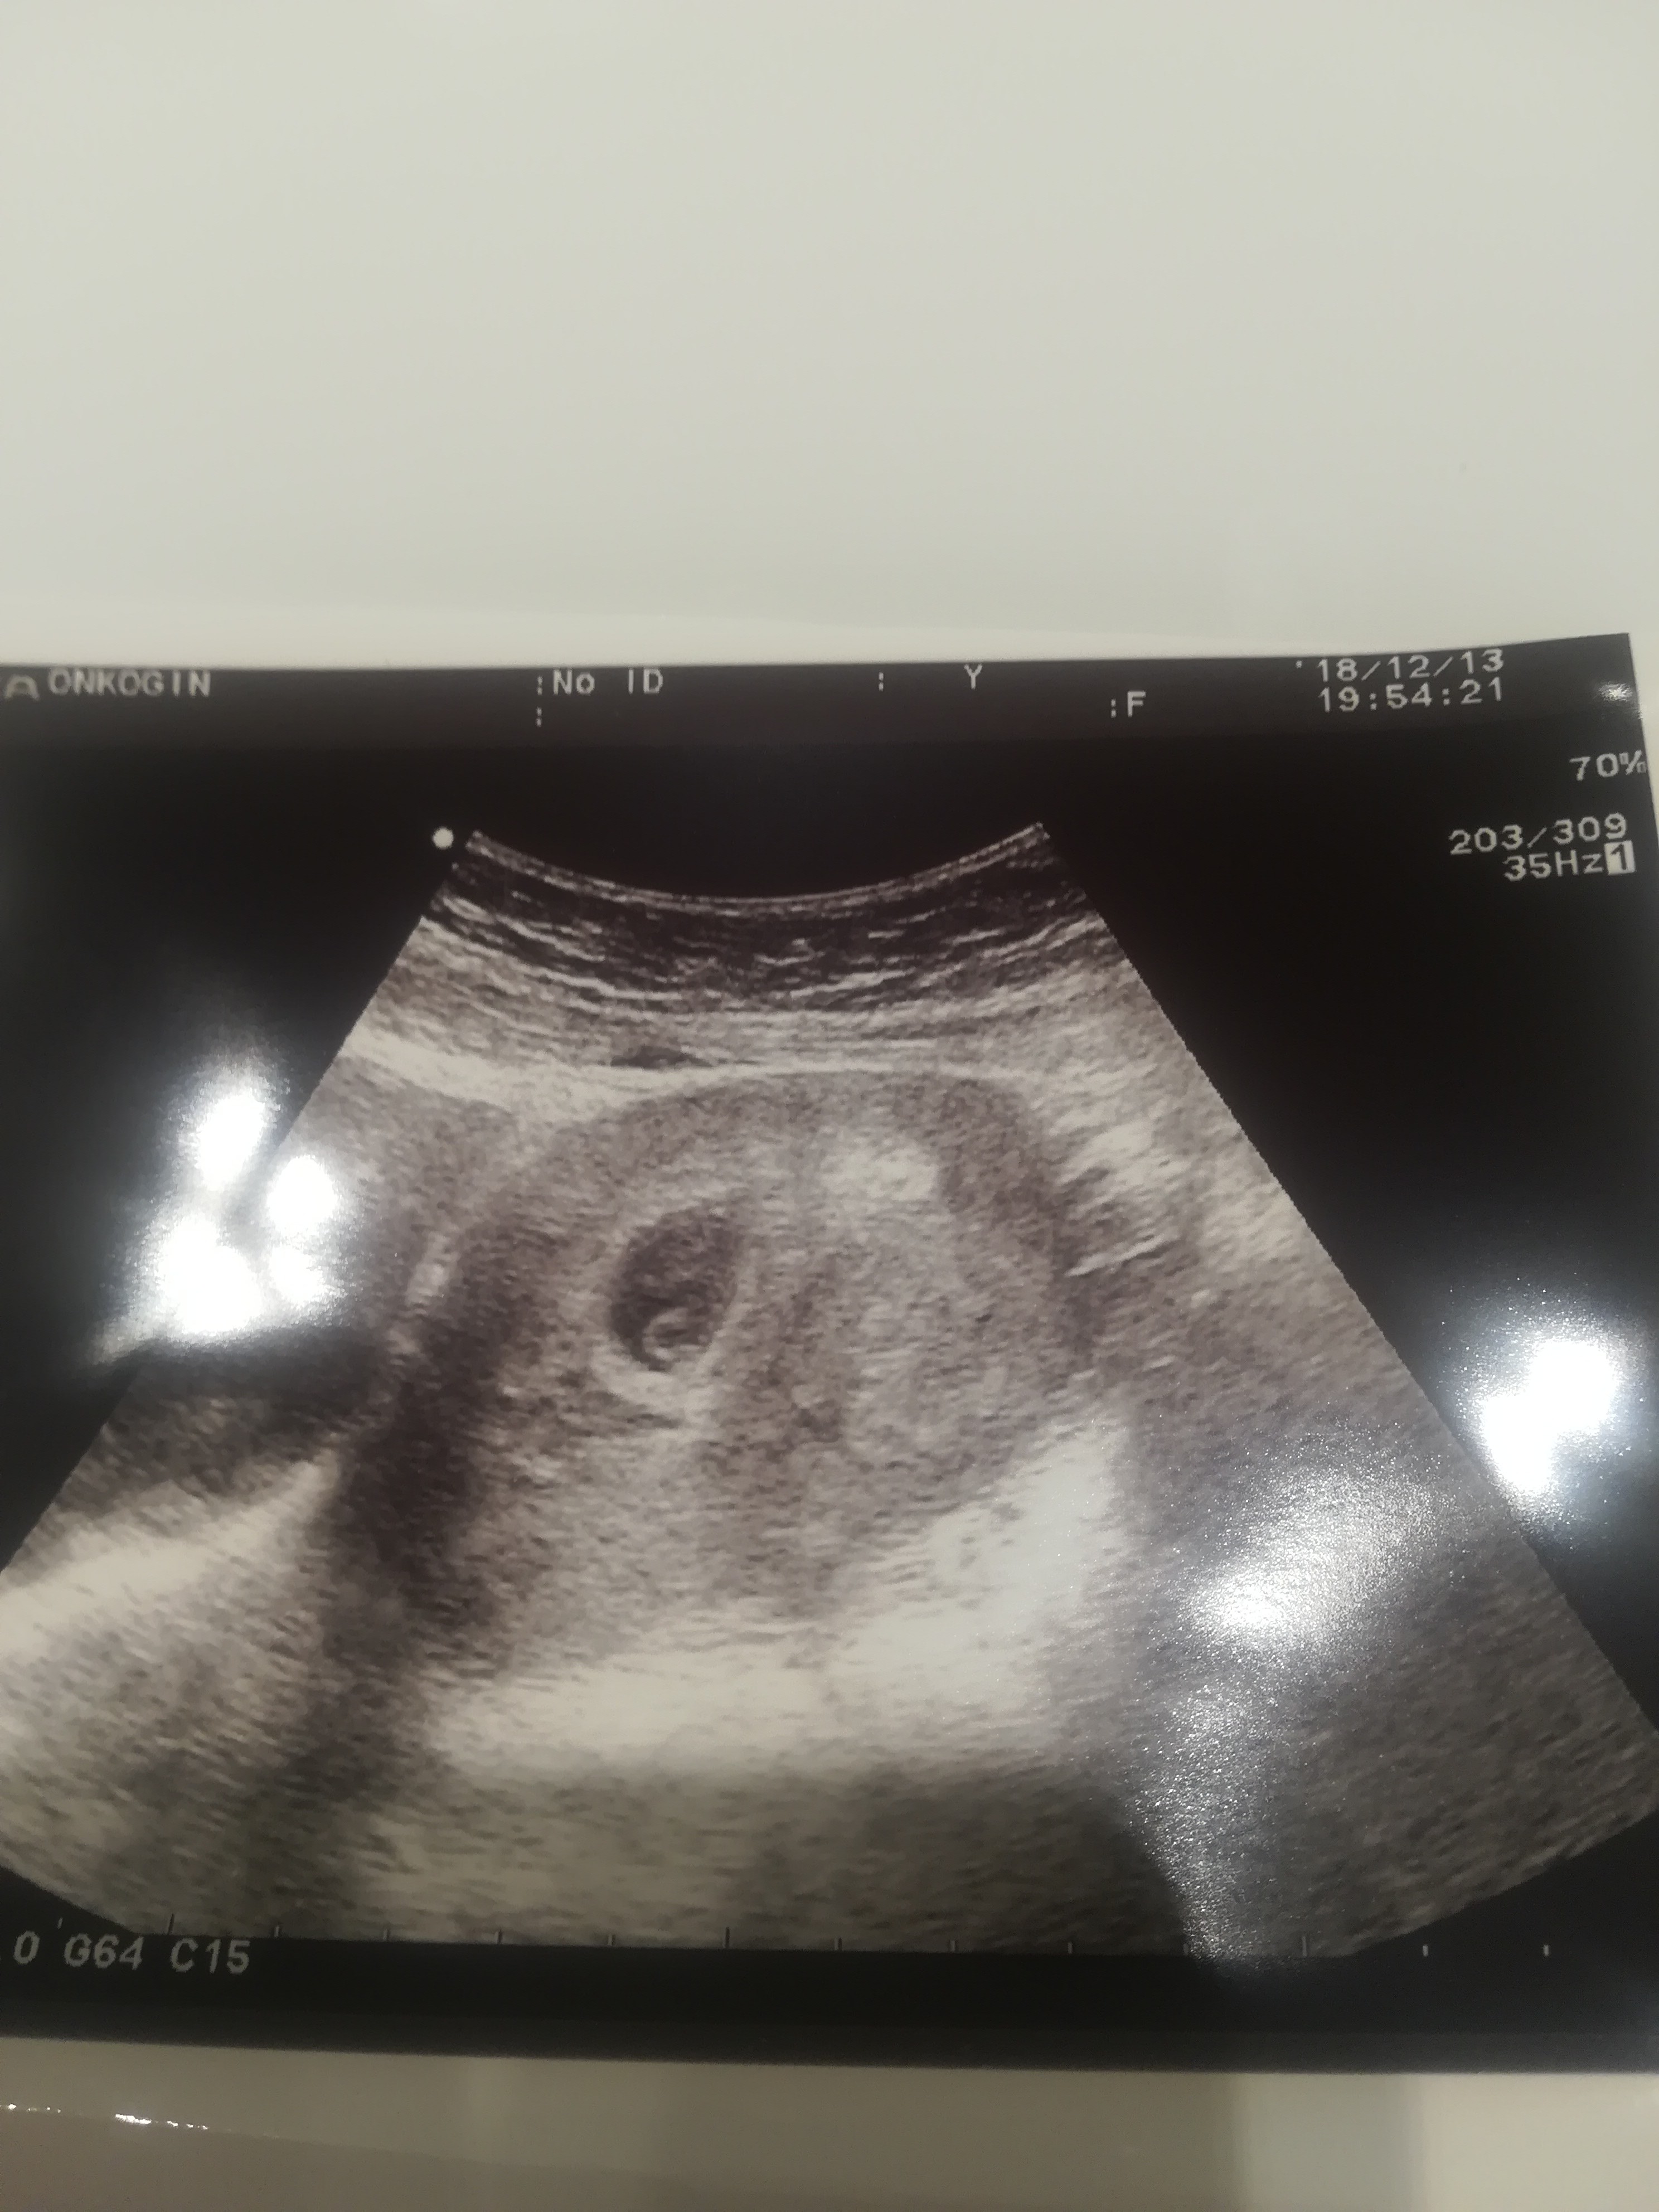

ja już po wizycie. Jest serduszko!!!!!

Mam kartę ciąży, termin mi wyliczył na 3.08 ale narazie zostaje z Wami